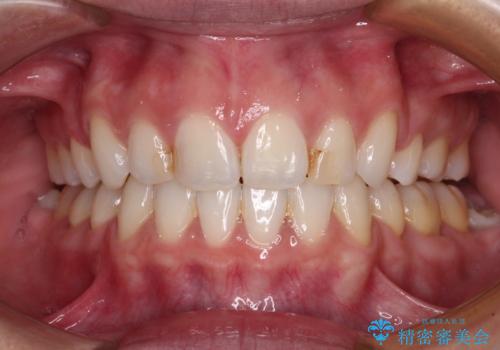

唇を閉じやすく 出っ歯の抜歯矯正

- くちばしのような前歯の突出感を気にして来院された患者様です。

抜歯矯正を行ったことで、顎先のつっぱり感や口元の閉じにくさを解消することができました。